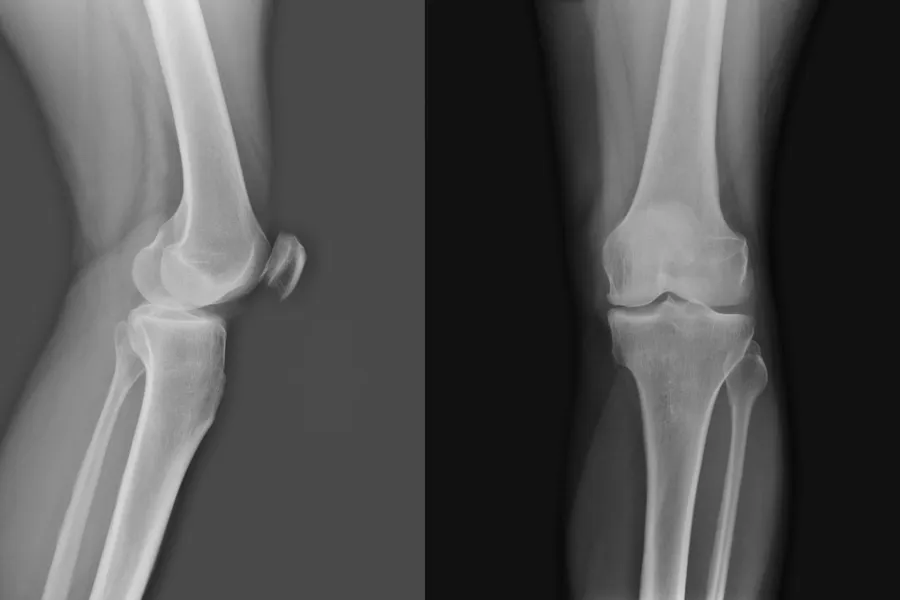

Kontroller av brudd og ortopedisk kirurgi: Ortopeder som trenger bruddkontroll av sine pasienter som bor på sykehjem kan vurdere om røntgen kan tas på sykehjem. Der det er aktuelt vil radiografene avtale med aktuelt sykehjem og ta bildene der. Ortopedene kan dermed følge opp pasientene sine digitalt, i samråd med sykehjemslege som kjenner pasienten.